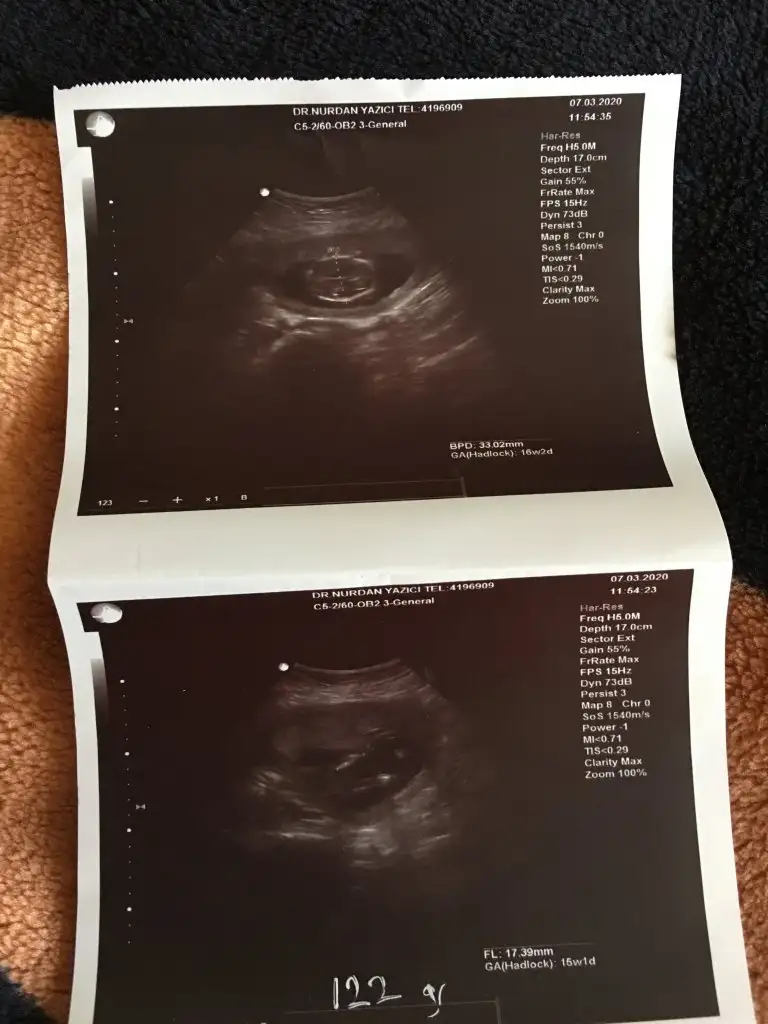

16 degil 11 -12 yada 13 haftalar olmalı dr söylemedimi sanki erkek gibi ama dediğim haftalara tahmin ediyorum

Kız sanki emin olamadım başka usgde paylaşınKızlar tahminde bulunabilirmisiniz ikiz bebekler 12 hafta 1 gunlikler